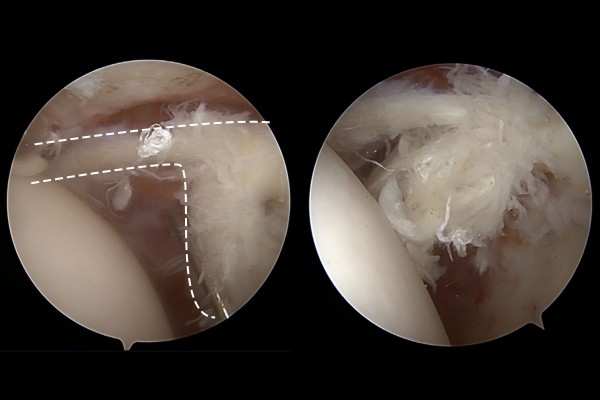

먼저 관절내시경을 이용해 어깨 내부를 확인했을 때, 이두근 장두가 얇아져서 거의 끊어지기 전 상태임이 확인됩니다.

이 경우에는 너덜너덜한 이두근 장두를 끊어서 새로운 부착지점에 튼튼하게 부착해줘야 하기 때문에 이두근 장두를 실로 묶어서 잡아준 후